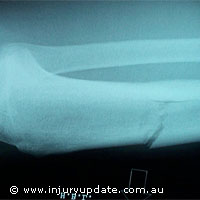

Novelscaff, un nouveau projet d'un montant de 1,2 million EUR, a débuté ses travaux sur la production d'os synthétiques et de parenchymes, un développement qui pourrait s'avérer prometteur pour les milliers de personnes touchés chaque année par la maladie et les traumatismes. À l'heure actuelle, lorsqu'un tissu osseux ou vasculaire est endommagé, il est remplacé par des greffes d'os ou de parties molles prélevés sur une partie du corps du patient. Mais la greffe d'os et de partie molle peut présenter des problèmes, comme l'explique Lisa Looney, Directrice du centre de recherche sur les traitements des matériaux de l'Université de Dublin et coordinatrice du projet Novelscaff: «Le tissu peut ne pas être disponible, et la 'double' procédure de deux opérations, l'une pour le prélèvement de l'os ou de la partie molle, et l'autre pour 'l'insertion' dans le site substitutif, présente un risque d'infection et de douleur plus élevé et prolonge les séjours en hôpital.» Au cours des 30 dernières années, une variété de substituts de greffes d'os synthétique et de partie molle a été mise à disposition. «Mais les applications n'ont pas été généralisées en raison de la difficulté à produire la structure et les propriétés du matériau optimales, de façon répétitive et contrôlable», a déclaré le Dr Looney. Financé au titre du programme Marie Curie de formation des jeunes chercheurs (Marie Curie Early Stage Training programme), le projet effectuera ses recherches, au cours des trois prochaines années, sur de nombreux procédés industriels innovants dans la perspective d'atteindre ce contrôle et cette répétitivité. Il tentera également de perfectionner l'architecture, la force et la texture des substituts de tissu et de mesurer la réponse des cellules vivantes à ces nouveaux substituts synthétiques. Pour le substitut de l'os, les chercheurs examineront des matériaux synthétiques tels que la biocéramique de phosphate de calcium mélangée à des biopolymères variés. Pour le travail vasculaire, des polymères spéciaux appelés hydrogels seront testés, lesquels gonflent dans l'eau pour former un matériau ayant l'aspect du gel et agissant en tant qu'échafaud.